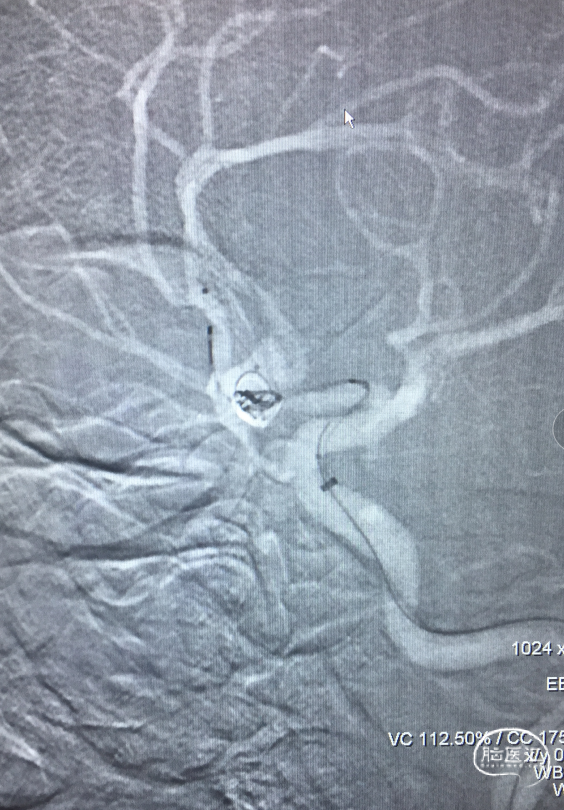

扩张术后造影:显示RACA血流恢复。

术后30分钟造影:LICA正侧位显示良好。

术后支架重建及蒙片:显示支架完全打开,贴壁充分,动脉瘤栓塞致密。